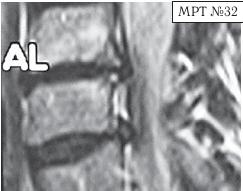

МРТ № 33 На МРТ отчётливо видны множественные очаги демиелинизации, вследствие развития нейроинфекции Этот случай очередной раз указывает на то, как даже гениальный мозг может пострадать от банальной глупости человеческой. Есть такие замечательные слова древнекитайского философа Лао-Цзюнь (Лао-Цзы) в «Рассуждениях о ста заболеваниях»: «Человек мудрости… избавляется от беды, когда она ещё не появилась. Ведь катастрофа рождается из мелочей, а болезнь возникает из тончайших отклонений». Грыжа Шморля Некоторых моих пациентов интересует вопрос, что такое грыжа Шморля, которая у них была обнаружена в результате обследования. Грыжа Шморля (хрящевой узелок Шморля, узелок Шморля) — это медицинский термин, который означает грыжевидное выпячивание, внедрение хрящевой ткани из межпозвонкового диска в губчатую кость тела позвонка. Названа она так в честь выдающегося немецкого патологоанатома, учёного, профессора Кристиана Шморля (Schmorl Ghristian Georg; 1861–1932), который первым описал данную патологию в рамках научного понимания начала XX века. За последние годы жизни учёный написал ценные работы по патологической анатомии позвоночника. В них профессор Шморль поделился рядом своих открытий, касающихся межпозвонковых дисков. В том числе там было описано состояние межпозвонкового сегмента, при котором межпозвонковым диском была продавлена замыкательная (гиалиновая) пластинка, отделяющая губчатую кость тела позвонка от межпозвонкового диска. Очаги данной патологии могут появиться у человека ещё в детском, подростковом возрасте. Как правило, они не имеют клинических проявлений, поэтому человек не чувствует каких-либо болевых ощущений. Но и здесь бывают свои исключения. На МРТ № 34 наблюдаются грыжи Шморля (обратите внимание на локализацию пульпозных ядер межпозвонковых дисков), при которых пациент не испытывает болевых ощущений. Данные грыжи опасений не вызывают. А вот на снимке МРТ № 35 наблюдаются грыжи Шморля с глубоким проникновением межпозвонковых дисков в тела позвонков со значительным разрушением последних. Это уже опасно. Тем более что у пациента остеопороз (дистрофия костной ткани, в результате которой кости становятся хрупкими и ломкими), что означает неизбежное прогрессирование данной патологии. А это, в свою очередь, увеличивает риск возникновения патологических переломов тел позвонков в местах развития грыж Шморля. Но не всё так уж и печально для данного пациента: если подлечить остеопороз, да в последующем бережно относиться к своему здоровью, то есть ещё шанс избежать серьёзных осложнений этого заболевания позвоночника. |